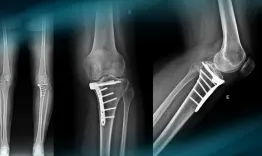

The goals of this clinical case are to discuss the different therapeutic options in case of vicious callus of the proximal tibia, to discuss the physical examination of an unstable knee, and to propose an innovative technique.

Management of a knee instability after ski trauma in a young woman​

Vincent Marot